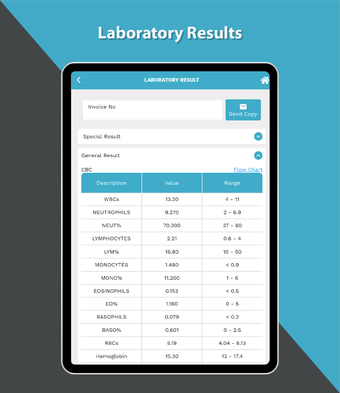

これは、Dr. Sulaiman Al-Habib Medical Services Groupが提供するすべてのサービスにアクセスするのを助ける無料のアプリです。グループの持続的なデジタル変革の重要な部分であり、効率と生産性の向上を重視しています。この新しいアプリは、オンライン医師相談から医療検査や放射線学の報告書まで、グループが提供するすべてのサービスに簡単にアクセスできるようになります。また、あなたと家族の医療記録を閲覧する機会も提供しています。